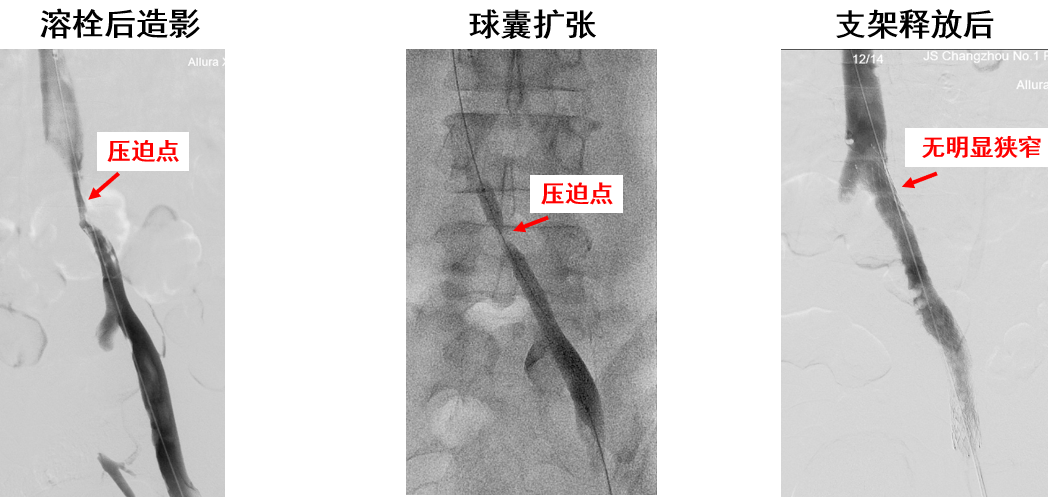

产品B:病例二(DVT合并Cockett综合征)

产品C:病例二(髂总静脉远端受压)

优点:

近心端斜口,防对侧血栓形成

近端闭环设计,支撑力较好

显影性能较好,便于精准定位

开环部分支撑力欠佳

因锥形设计,远端尺寸小,支架选择困难,远端易出现支架“悬空”现象

近段闭环打开后无法回收